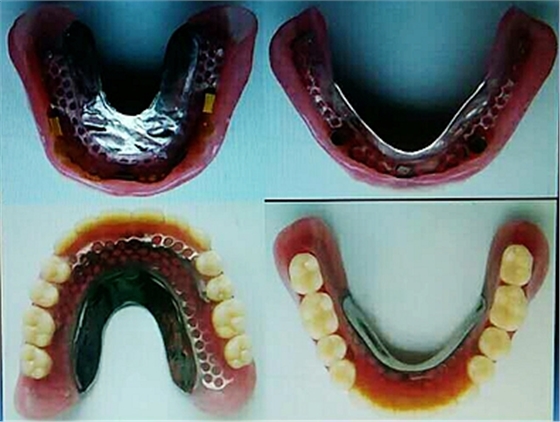

毛國(guó)斌種植病例——群討論分享

Screenshot_2017-04-25-09-45-02.pngScreenshot_2017-04-25-09-46-19.pngScreenshot_2017-04-25-09-51-57.pngScreenshot_2017-04-25-09-52-41.pngScreenshot_2017-04-25-10-06-38.pngScreenshot_2017-04-25-10-09-20.png

Screenshot_2017-04-25-10-12-47.pngScreenshot_2017-04-25-10-16-29.pngScreenshot_2017-04-25-10-19-08.pngScreenshot_2017-04-25-10-22-02.pngScreenshot_2017-04-25-10-26-11.pngScreenshot_2017-04-25-10-26-35.png

Screenshot_2017-04-25-10-34-15.pngScreenshot_2017-04-25-10-37-02.pngScreenshot_2017-04-25-10-38-17.pngScreenshot_2017-04-25-10-43-56.pngScreenshot_2017-04-25-10-45-02.png

mmexport1493090938783.jpgmmexport1493090943165.jpg

mmexport1493090947523.jpgmmexport1493090952079.jpg

mmexport1493090960504.jpgmmexport1493090963186.jpg

mmexport1493090967371.jpgmmexport1493090969886.jpg

mmexport1493090972304.jpgmmexport1493090974802.jpg

mmexport1493090981101.jpg

mmexport1493090983321.jpgmmexport1493090991830.jpg

mmexport1493090994026.jpgmmexport1493090985721.jpg

mmexport1493091008273.jpgmmexport1493091010574.jpg

江思玉整理群種植病例